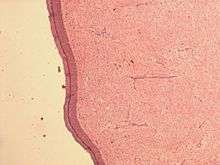

| Micrograph of an atrial myxoma. H&E stain. | |

A myxoma (New Latin from Greek 'muxa' for mucus) is a myxoid tumor of primitive connective tissue.[1] It is the most common primary tumor of the heart in adults, but can also occur in other locations.